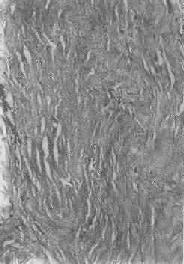

肝淀粉样变

图1-22 肝淀粉样变

淀粉样物质呈均质状,沉着于窦内皮下,肝细胞索受压萎缩

5.淀粉样变性 组织内有淀粉样物质沉积称为淀粉样变性(amyloid degeneration,amyloidosis)。淀粉样物质为一种结合粘多糖的蛋白质,遇碘时被染成赤褐色,再加以硫酸则呈蓝色,与淀粉遇碘时的反应相似,故称之为淀粉样物质。此物质常浸润于细胞间或沉积于小血管的基底膜下,或沿网状纤维支架分布(图1-22)。淀粉样物质在HE染色切片中为淡红色均质状,电镜下则为纤细的丝状。